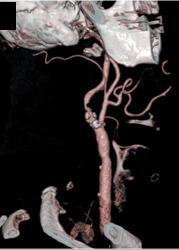

Carotid Artery Stenosis